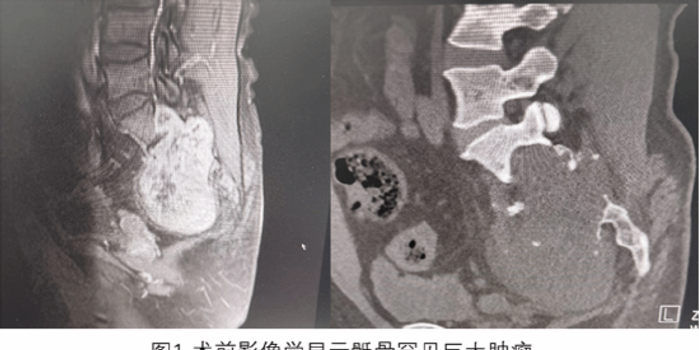

患者为一名中年男性,长期饱受疼痛困扰,并出现持续的盆腔压迫症状。经过多次检查,诊断结果显示患者患有一颗直径约10厘米的巨大骶骨肿瘤。肿瘤不仅包绕了腰骶部的椎管内神经,还向盆腔延伸,压迫了多个脏器,极大影响了患者的日常活动能力和生活质量。

骶骨肿瘤被医学界普遍认为是脊柱肿瘤中的“终极挑战”,其手术风险和难度都非常大。该患者肿瘤包绕骶神经,手术中可能需要牺牲部分神经以切除肿瘤,这可能会导致患者术后下肢功能障碍、大小便失禁等严重后遗症。另一发面,术前检查显示,肿瘤与髂血管密切相邻,术中如果血管发生损伤,可能会引起大量出血,增加手术难度。此外,由于骶骨本身血供丰富,手术过程中出血量通常较大,往往超过5000ml,这进一步加大了手术的风险。